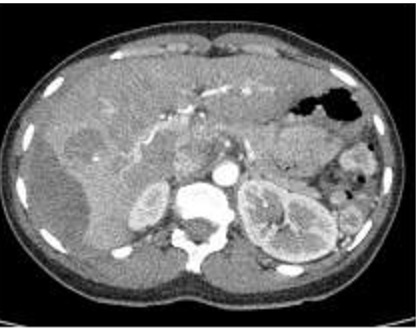

Image TDM du foie en coupe

axiale a travers la vesicule biliaire ( avec

contrast ) . Veine porte , vesicule biliaire sont en

voyait |